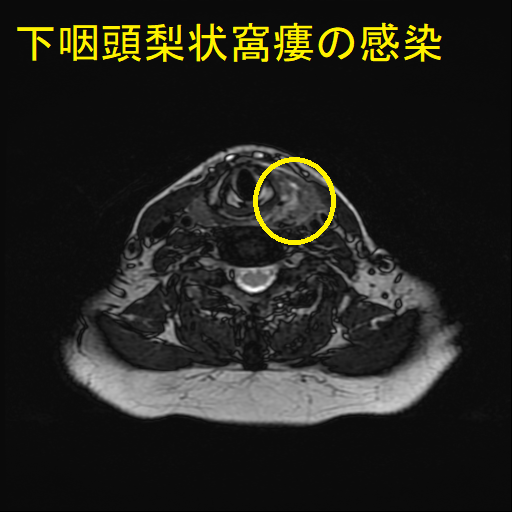

- 通常の造影頸部CTで、甲状腺外の膿瘍形成と、その範囲が明らかになります。

- 下咽頭部造影CTで、下咽頭梨状窩瘻を見つけます。

急性化膿性甲状腺炎に至らない下咽頭梨状窩瘻の感染もあります。下咽頭梨状窩瘻が甲状腺内でなく、甲状腺周囲に開口している場合に起こります。